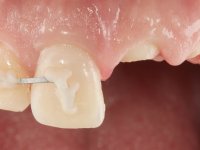

Paciente do sexo masculino, com 29 anos não fumador. Após atendimento hospitalar, na sequência de um traumatismo facial, surgiu na consulta com os dentes 2.1 e 2.2 com extensas fraturas coronais e com exposição pulpar. As fraturas eram justa-ósseas a nível palatino e as raízes apresentavam mobilidade acentuada. Os dentes 1.3,1.2 e 1.1 apresentavam-se ferulizados com um arame ortodôntico. A ferulização abrangia as superfícies vestibulares e palatinas. Os três dentes em conjunto também apresentavam mobilidade. O lábio inferior apresentava-se ainda suturado e a higiene oral era sofrível.

Foi feito o tratamento endodôntico dos dentes 2.1 e 2.2.de imediato, a sintomatologia que o paciente manifestava a isso impunha. Na mesma consulta foi realizada uma extensa gengivetomia com o bisturi elétrico, no sentido de expor os limites cervicais da fratura. Foram colocadas resinas compostas nos remanescentes radiculares com a intenção de reformular a emergência dos tecidos moles. Realizei a impressão dos remanescentes radiculares para confeção em laboratório de uma ponte provisória. A ponte provisória de 2 elementos, apresentava um formato que visava no futuro acomodar o coto dos espigões falsos cotos que iria ser cimentados nos remanescentes radiculares. Apresentava um reforço metálico palatino e dois apoios para os dentes adjacentes, um mesial e outro distal. Os remanescentes radiculares foram preparados para a confeção de dois espigões falso coto fundidos. As linhas de acabamento cervical foram definidas e os canais radiculares desobturados e preparados. A impressão foi realizada com a utilização de tutores de plástico com a técnica de dupla mistura. O afastamento gengival foi feito utilizando pasta de caolino. A ponte provisória foi rebasada em boca com acrílico auto polimerizavel, cimentada provisoriamente sobre as raízes e os apoios colados aos dentes adjacentes. No laboratório foram confecionados os E.F.C. fundidos, tendo o cuidado de preservar espaço para a definição no re preparo dentário da linha de acabamento cervical. Removida a ponte provisória foi feita a cimentação dos E.F.C. fundidos com cimento de ionómero de vidro reforçado com resina. A ponte provisória teve que ser retocada para permitir a acomodação dos cotos e simultaneamente foi readaptada à redefinida linha de acabamento cervical. Durante 2 meses a ponte provisória acompanhou a estabilização periodontal das raízes traumatizadas e simultaneamente conseguiu a maturação da arquitetura gengival.